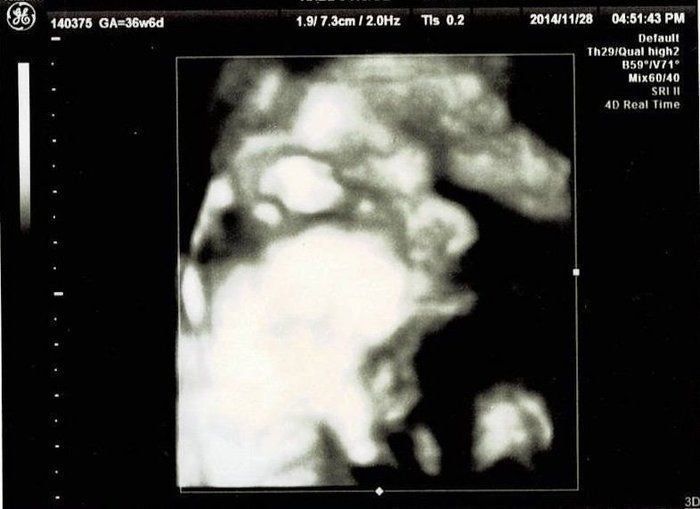

おなかの中はどうなっていくの? エコー写真で振り返る、高齢ママのはじめての妊娠生活 -